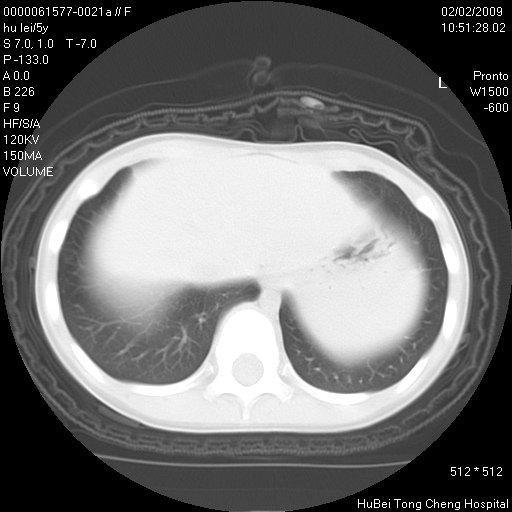

标题: PED1732:M5Y,右肺囊性占位!

患者:男,5。无明显不适,拍胸片考虑右肺囊肿。

行ct扫描,图象如下:

右肺巨大囊肿或包虫

考虑先天性巨大支气管肺囊肿,建议包虫实验除外肺包虫。

右肺巨大囊性占位性病变;考虑巨大肺囊肿,不排除淋巴管瘤可能。

病灶与前胸壁和右上纵隔、叶间裂界限不清,病灶前缘及内侧缘看不到正常的肺组织,不能排除包裹性积液。